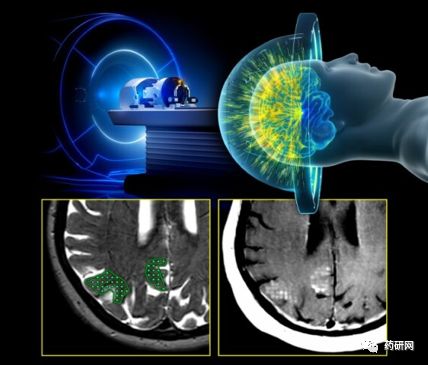

放疗联合小分子药物可显著降低1年内疾病进展

医药新闻

新闻

1月15日 13:58

0

243

9